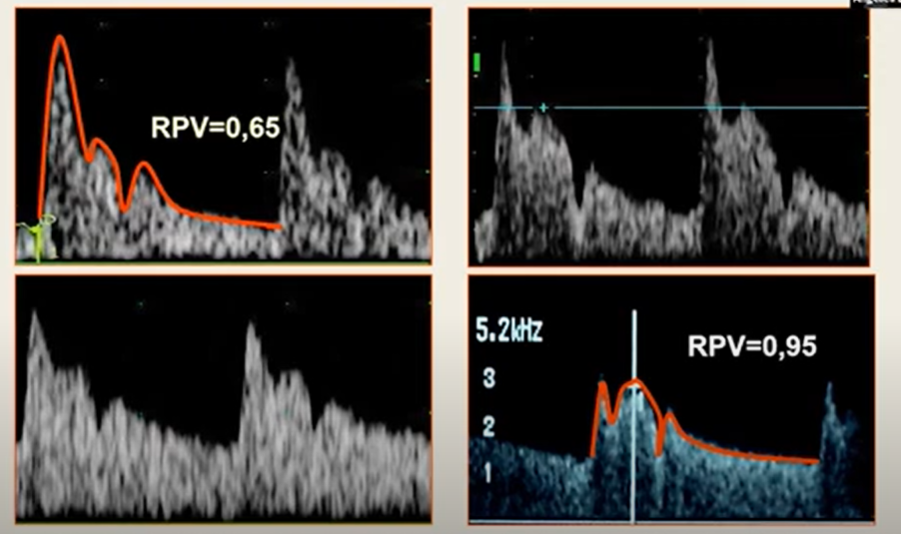

- O traçado da artéria oftálmica apresenta um pico sistólico, uma desaceleração (na sístole) e um novo pico sistólico (ainda na sístole), e um ponto inferior que representa o fechamento da válvula aórtica. Diferenciar a artéria oftálmica das artérias ciliares, estas últimas possuem pico sistólico baixo.

- O pico sistólico da artéria oftálmica é de pelo menos 20cm/s

Diferenciar a artéria oftálmica das artérias ciliares, estas últimas possuem pico sistólico baixo.

- Razão PSV2/PSV1.

- Pré-eclâmpsia leve: redução discreta de PI e RI, aumento moderado da razão PSV2/PSV1.

- Pré-eclâmpsia grave: redução acentuada de PI e RI, aumento significativo da razão PSV2/PSV1.

- A magnitude das alterações correlacionou-se à gravidade da doença.

As gestantes com pré-eclâmpsia apresentam alterações características na hemodinâmica cerebral refletidas no Doppler da artéria oftálmica. A redução de PI/RI e o aumento da razão PSV2/PSV1 podem ser usados como marcadores indiretos da gravidade.